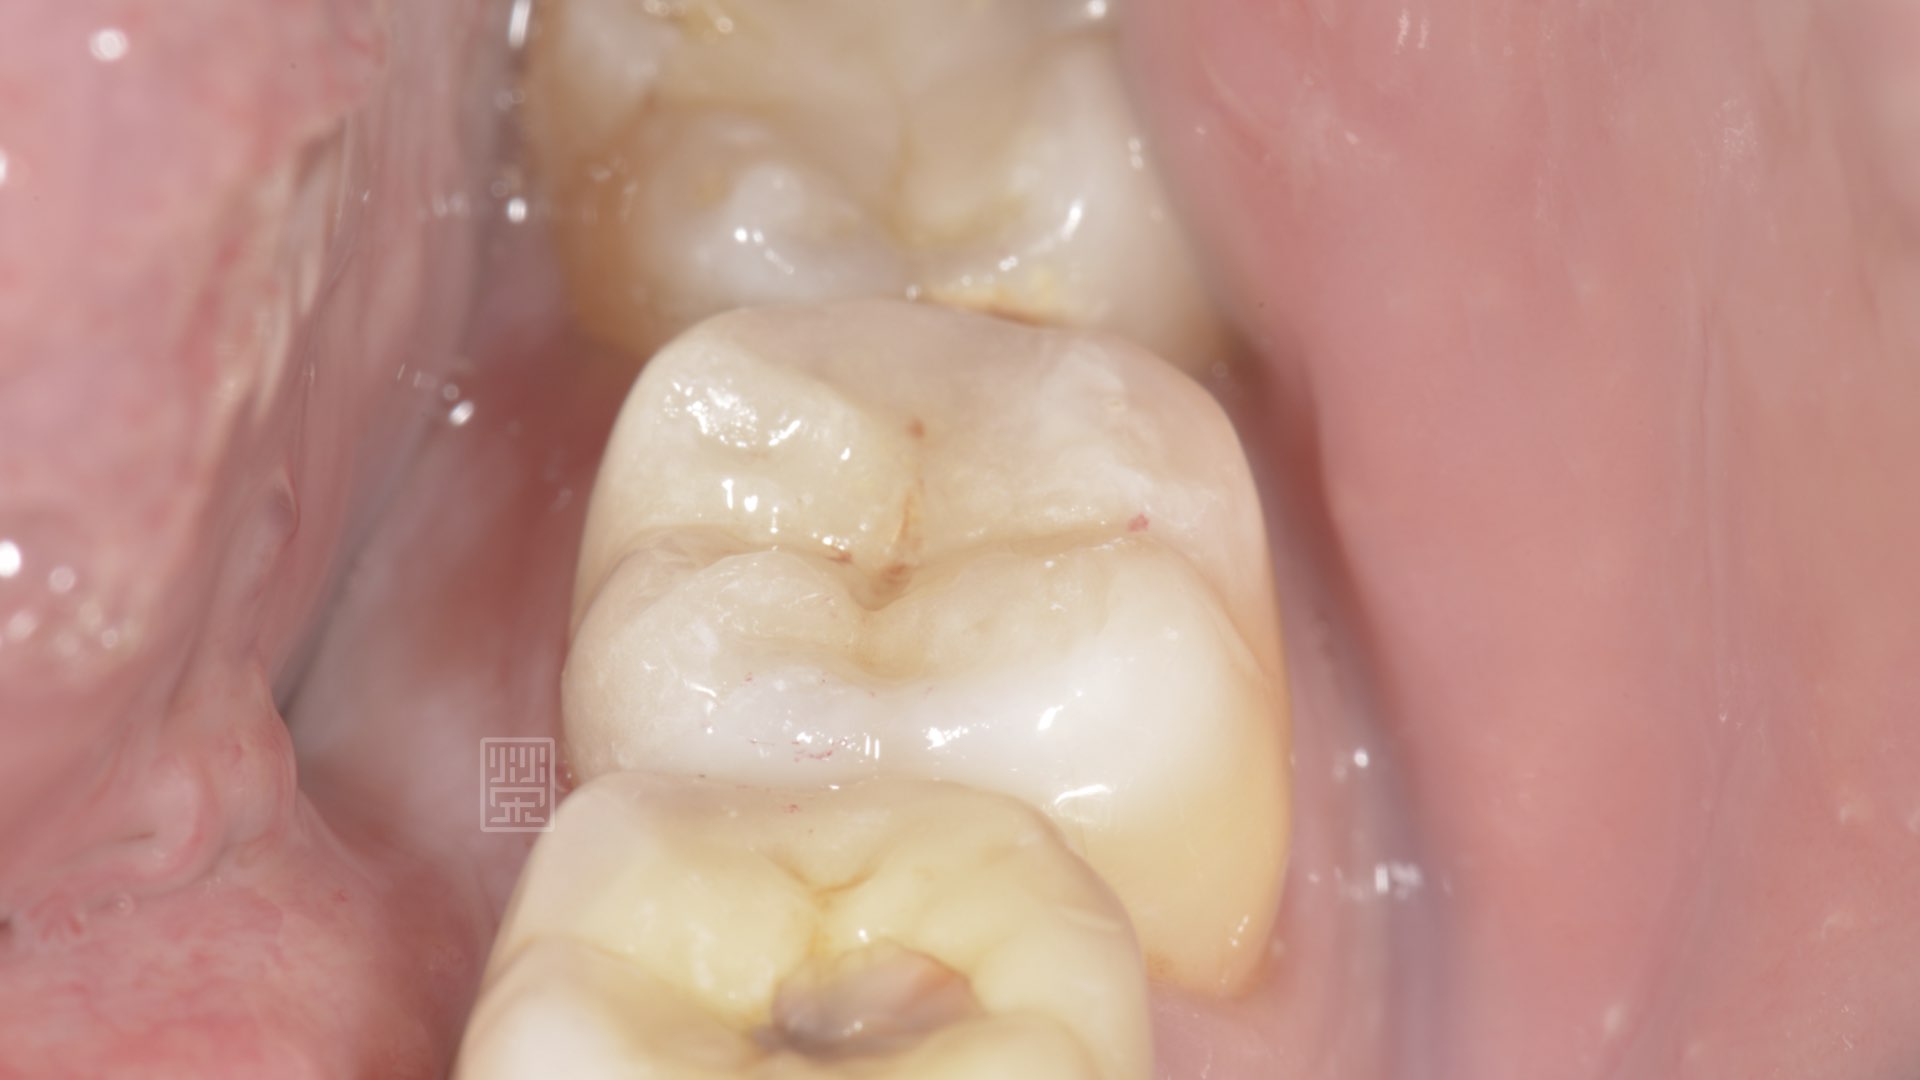

牙齒裂痕